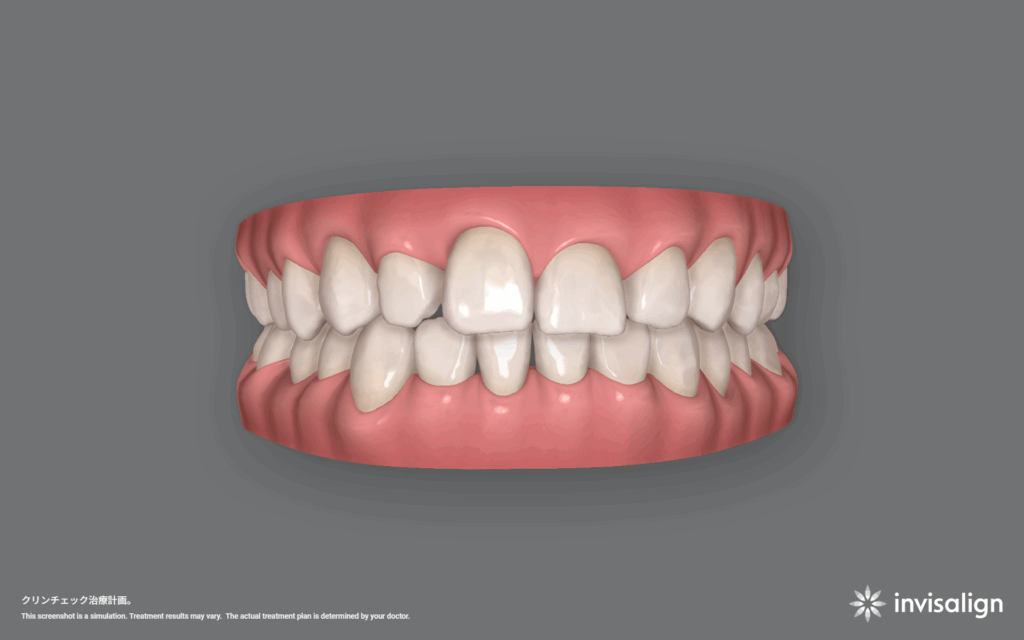

ビザライン矯正治療。46ステージ。治療費766,700円+調整料(初回)16,500円+調整料5,500円×回数+リテーナー55,000円。

1日20時間以上装着、1ステージ10日間。つまり460日、約15ヶ月、約1年3ヶ月の計画です。

この状態を目指して、患者さんと一緒に頑張っていきます。